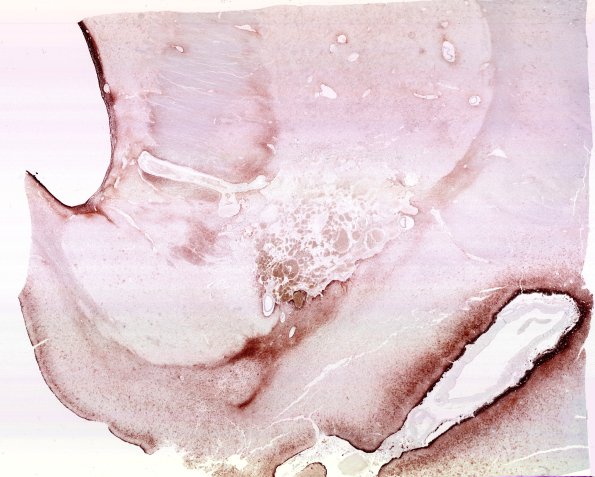

31H1 Cavernoma (Case 31) GFAP WM

31H1,2 GFAP immunoreactivity is excluded from the interior portions of the cavernoma. (GFAP IHC)